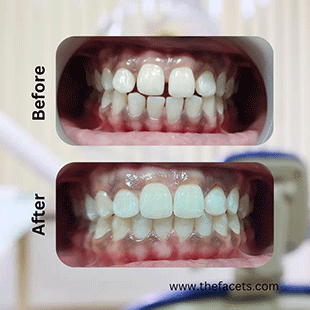

Expert Gap Closure Dentistry in Kochi, Kerala

Close the Gap. Love Your Smile. Trusted Dental Care in India.

Whether you're from Kerala or visiting India for high-quality, affordable dental treatment, our advanced gap correction solutions are safe, aesthetic, and long-lasting. Discover personalized smile correction at Facets Dental Clinics in Kochi – Kerala's leading preventive dental aesthetic network in association with D4k Dentistry